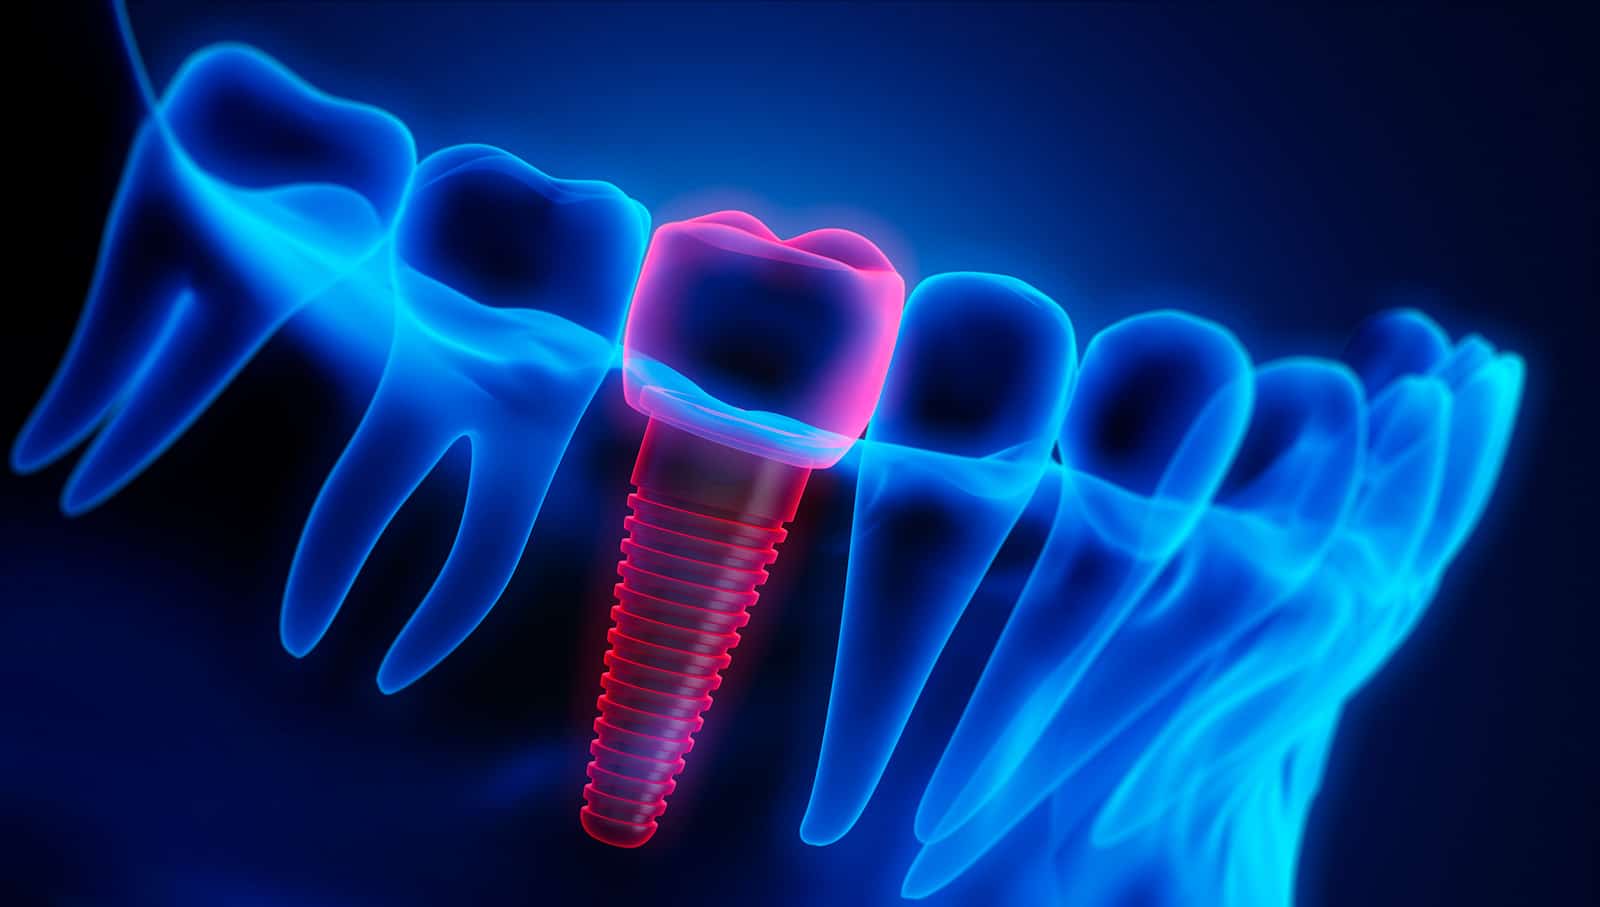

Implants are the best solution for simulating the look, feel, and function of natural teeth. Dental implants do much more than replace missing teeth. They help maintain and strengthen bone structure, provide the ability to chew healthy food and give patients the confidence to smile. They also protect existing teeth by helping to preserve bone structure.

Once a tooth is lost, several things begin to happen that are not immediately noticeable to a patient and can have a significant negative effect on both health and appearance. Tooth roots help hold teeth in place, but they are also critical in maintaining health in the surrounding gums and supporting bone structures. Bone loss in the jawbone is one significant problem that naturally occurs once a tooth is lost. This bone loss can compromise the integrity of neighboring tooth roots and tooth stability, and it is also a large part of what causes the “sunken” look that is seen in people who have lost several or all of their teeth. It is the reason patients who wear dentures find that over time their dentures are harder and harder to fit and keep in place.

Dental implant placement can help generate bone growth in the area around the implant, which not only strengthens the bone and builds support, but can also alleviate the sunken look that can occur with bone loss in the jaw. This process is known as osseointegration and is a significant benefit of implant placement because it can also help prevent future bone loss.